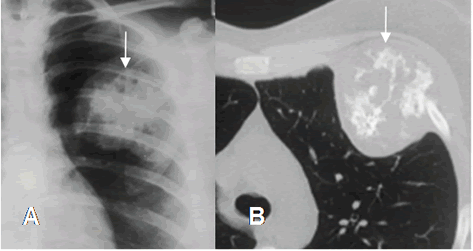

Fig 46. Condrosarcoma.

A: Rx PA. Imagen redondeada y de bordes definidos, proyectada sobre el campo pulmonar superior izquierdo.

B: TAC axial. Imagen lítica y expansiva del arco costal, con calcificación condroide la matriz, que corresponde a condrosarcoma.